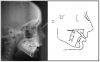

Cephalometric (lateral skull) radiograph: A lateral view of the skull, the cephalometric radiograph is used to study the relationship of the bones, teeth and jaws to the face and skull (Figure 21). The orthodontist obtains measurements then compares them to a standard reference group.

Cephalometric radiographic images taken before, during, and after treatment can be superimposed to study changes in jaw and tooth position. Although the main purpose of taking radiographic images is not for pathology screening, they can sometimes reveal changes or anomalies in the cervical spine, skull, jaws, or cranial base.

Figure 21. Cephalometric radiographic images can be superimposed to study changes in jaw and tooth position.

Figure 21